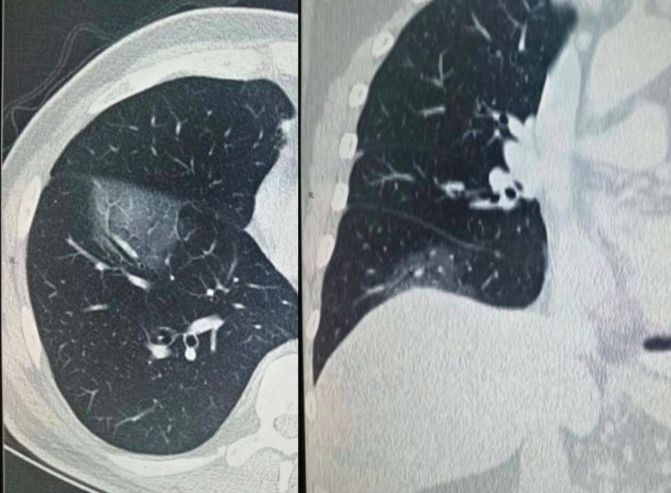

这是一位 57 岁男性。起病初期仅有畏寒,2 天后出现午后低、中热(37.5°C-37.7°C), 下呼吸道分泌物(痰)2019-CoV 阳性,服用抗格兰阳性抗生素和阿比多尔 3 天后症状缓解。[1]